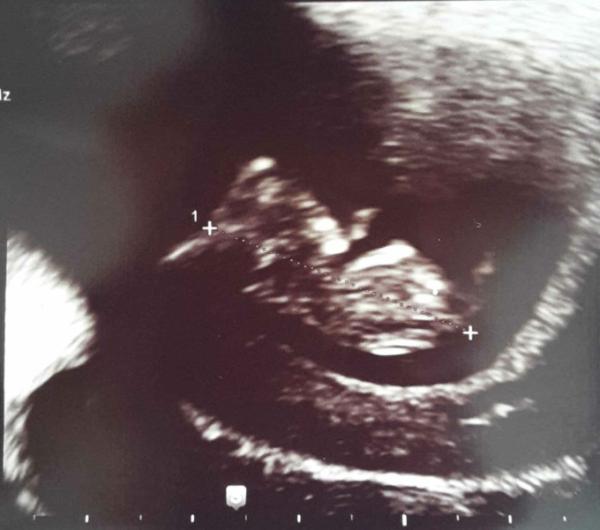

Hallo Ihr lieben, bin gerade vom 2. US Termin zurück. Es ist alles zeitgemäß. Das Würmchen ist jetzt 2,7 cm groß Es hat ganz viel rumgezappelt mit dem ärmchen und Beinchen die ganze Zeit Mutterpass hab ich jetzt auch. Bin heute bei 9+5.

Der erste Kommentar meines Mannes "sieht aus wie ein T-Rex Baby"

Super Bild was man da schon alles erkennen kann. Einfach schön